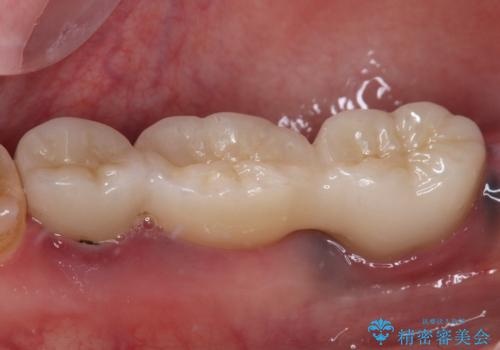

- ブリッジが装着されている奥歯がぐらぐらするとのことで来院された患者様です。

診察を行ったところ、手前の歯は歯根が破折しており、抜歯が必要な状態でした。

左右ともに臼歯部しか咬んでおらず、ブリッジの手前側の歯が破折したことで大きく揺さぶられてしまい、奥側の歯も周辺の歯が著しく吸収し、抜歯が必要な状態でした。

ブリッジの支台歯2本を抜歯し、反対側の咬合負担を軽減するために、通常よりも短い待機時間で2本のインプラントを埋入することとしました。